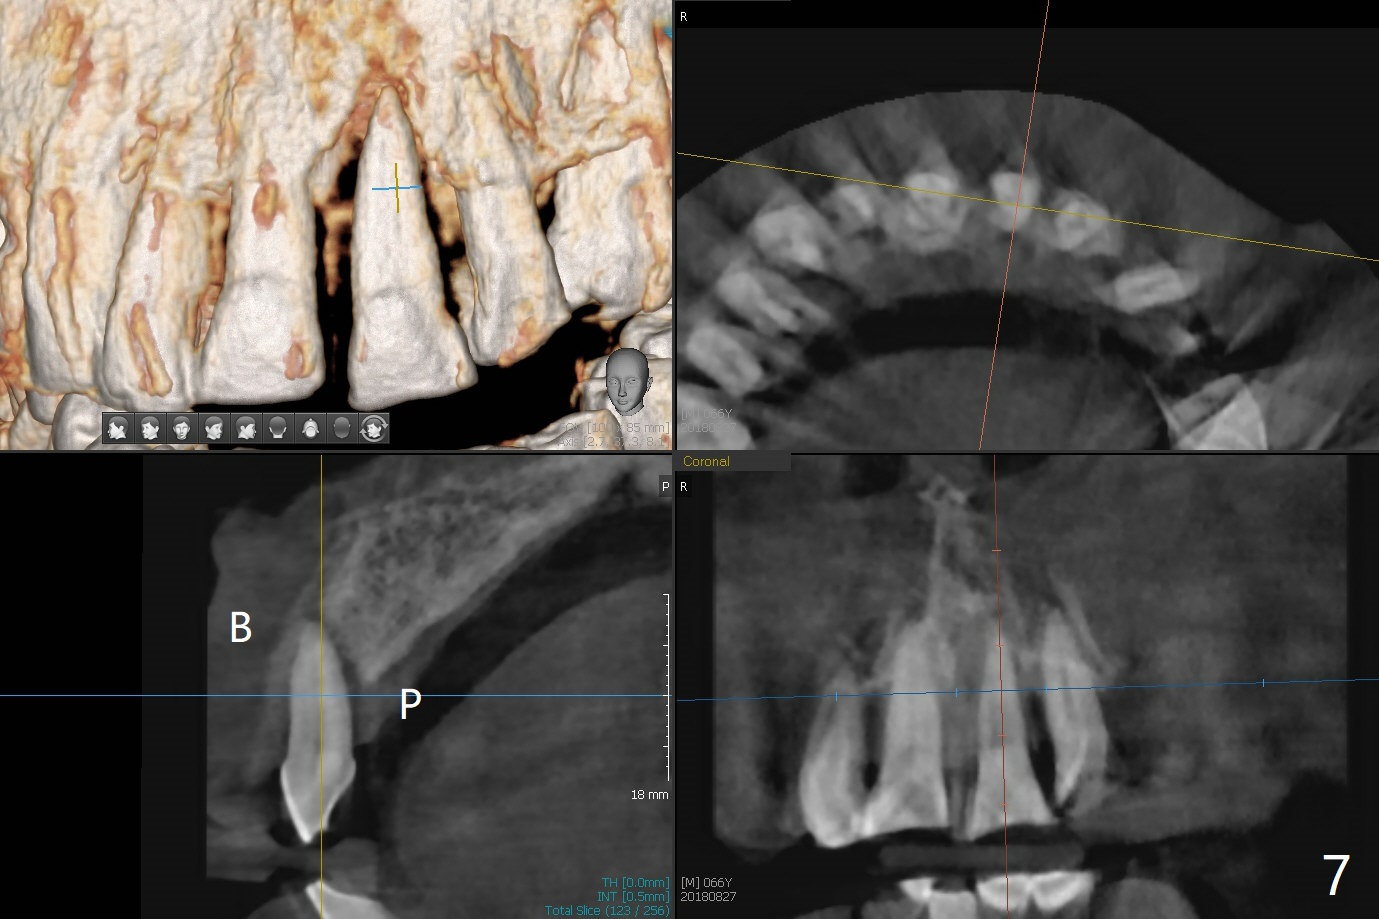

A 67-year-old man requests extraction of the loose tooth #9 (Fig.1). After extraction, the labial plate is found to be missing. With incision, allograft is kept in place with a 12x24 mm anterior narrow Cytoplast and 4-0 Chromic gut suture (Fig.2). Periodontal dressing dislodges in 2 days. The wound dehisces transversely 5 days postop (Fig.3 arrows), whereas the wound was open buccopalatal when the sutures were placed. Probably due to extensive dissection, the erythematous mucosa is large (Fig.4), although asymptomatic. When X-ray shows V-shaped bony defect (Fig.1 (PA), 5 (Pan), 6 (CT)), do not dissect the overlying thin buccal gingiva, which is most likely to dehisce. In fact immediate implant with guide appears to be more conservative, since there is no pressure against the buccal gingiva (Fig.7,8). To be more ideally, the implant could be placed more coronally, longer (13 mm instead of 11.5, Fig.9,10) and narrower (3.5 mm instead of 4.0 mm, Fig.11 (red circles: bone graft)).